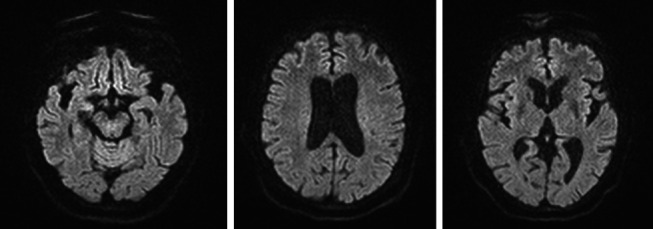

Introduction: Gliomatosis cerebri (GC) is a diffuse neoplastic process, whose presentation is extremely rare and lacks a characteristic clinical pattern. The objective of this case is to describe the clinical aspects of a patient with GC, in whom symptoms of parkinsonism and neurocognitive issues predominate. Case Report: A 78-year-old patient with no significant medical history was referred to the neurology consultation due to balance disturbances accompanied by head tremor. Symptoms of parkinsonism progressively worsened, adding cognitive and neuropsychiatric disorders. Cranial magnetic resonance imaging (MRI) showed diffuse and generalized white matter hyperintensity. Under the suspicion of GC, a frontal lobe biopsy was performed, with a pathology report of diffuse astrocytoma, thus confirming the diagnosis of GC. Conclusion: GC is a disease that presents with nonspecific clinical manifestations, making a clinical diagnosis challenging. It should be suspected in cases of parkinsonism accompanied by other focal neurological disorders. This leads to delayed diagnosis and consequently low incidence. The importance of MRI as a diagnostic aid is highlighted, with biopsy being necessary to confirm the diagnosis.

脑胶质瘤病(Gliomatosis cerebri, GC)是一种弥漫性肿瘤,其临床表现极为罕见,缺乏特征性的临床模式。本病例的目的是描述GC患者的临床方面,其中帕金森症状和神经认知问题占主导地位。病例报告:一名78岁无明显病史的患者,因平衡障碍伴头部震颤而就诊神经内科。帕金森氏症的症状逐渐恶化,增加了认知和神经精神障碍。颅脑磁共振成像显示弥漫性广泛性白质高信号。在怀疑为胃癌的情况下,行额叶活检,病理报告为弥漫性星形细胞瘤,确诊为胃癌。结论:胃癌是一种临床表现非特异性的疾病,临床诊断具有挑战性。在帕金森病合并其他局灶性神经系统疾病的病例中应怀疑。这导致诊断延迟,从而降低发病率。MRI作为诊断辅助的重要性被强调,活检是必要的,以确认诊断。